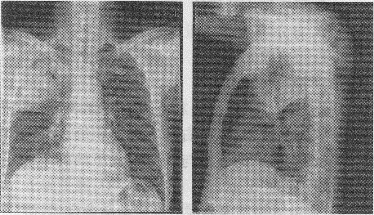

患者,男,53歲,發熱、咳嗽、咳痰3天,查體:體溫38.6℃,右上肺叩濁。胸片如圖:

正確答案:5.B;6.C;7.D;8.D 解題思路:  1.結合急性發作的病史及肺葉實變的影像表現,大葉性肺炎為最可能診斷。

2.本病例處于大葉性肺炎的實變期(即病理的紅色肝樣變或灰色肝樣變期)。

3.如患者有免疫力低下的情況(如糖尿病多年病史)則應考慮干酪性肺炎的可能。

4.大葉性肺炎的致病菌為肺炎雙球菌。